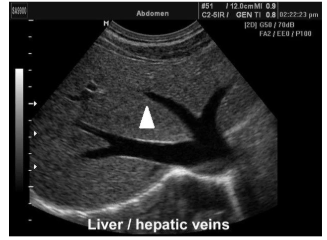

Assinale a alternativa CORRETA para qual segmento hepático encontra-se a marcação com triângulo: